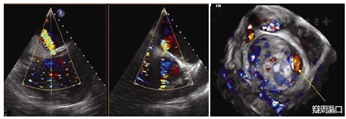

男,55岁。因"主动脉瓣、二尖瓣机械瓣置换术后11年,间歇性胸闷、气短2个月"收治入院。既往病史:2008年6月,因"风湿性心脏病、主动脉瓣关闭不全、二尖瓣狭窄伴关闭不全"于当地医院行主动脉瓣、二尖瓣机械瓣置换术。术后并发Ⅲ度房室传导阻滞,于2009年3月行心脏永久起搏器置入术。2个月前因上呼吸道感染后突发胸闷、气短,复查超声心动图提示:二尖瓣机械瓣瓣周漏,二尖瓣瓣周大量反流,中度肺动脉高压。入院后予以药物治疗改善心脏功能,稳定病情。经食管超声心动图提示:主动脉瓣、二尖瓣机械瓣置换术后,二尖瓣机械瓣2~3点位见3 mm间隙,瓣周反流7 ml(图1)。经心脏团队评估,患者系二次外科开胸手术高危患者(EuroScore Ⅱ评分10.2分,STS评分8.5分),经与患者及家属积极沟通后,决定行经皮心尖穿刺微创二尖瓣瓣周漏封堵术。该技术已通过我院临床伦理委员会审批(编号:KY20150205-1),术前常规签署手术相关知情同意书。